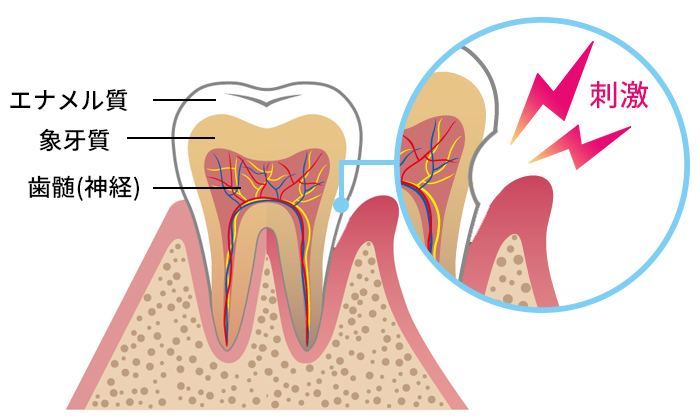

歯の最表層にあるエナメル質は削っても痛みを感じることはありません。象牙質はその内層にあり、また根部ではエナメル質がなく全層が象牙質でできています。象牙質は器具でこすったり、冷たいものや熱いもの等に触れると、その刺激は内部の神経に伝達されて、歯は痛みを感じます。つまり象牙質は痛みを感じる部分です。通常、象牙質はエナメル質に覆われているので、こうした痛みを感じることはありませんが、極端に冷たいものなどではエナメル質の上からでも温度が内部の象牙質に伝わって、歯が痛みを感じることもあります。しかし、様々な理由で象牙質が露出すると、刺激が神経に伝達されやすくなり、知覚過敏が生じるようになります。

象牙質が内部の神経にまで刺激を伝えるのは、象牙質の中にある無数の小さな管状の構造物があることによります。この小さな空隙は加齢などにより、少しずつ塞がってくることもあります。このような場合には知覚過敏は起きません。したがって象牙質が露出している時には必ず知覚過敏が起きるということではありません。